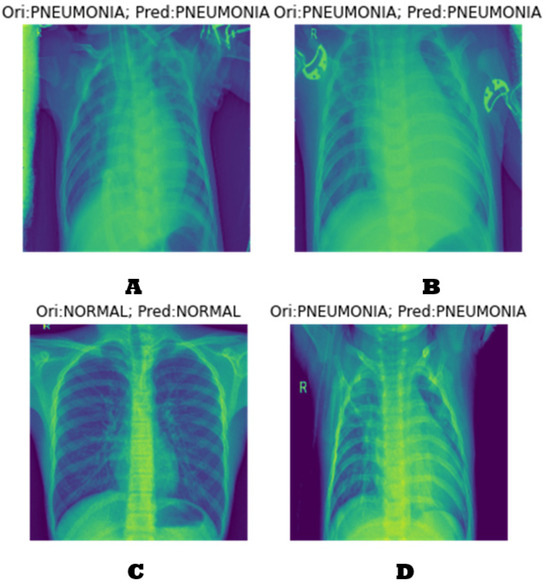

4.1. Generating the DCGAN Image

- Part 1: the discriminator is trained to maximize the probability of correctly classifying the given input as either real or fake.

- Part 2: the generator is trained by minimizing log (1-D(G-(Z))) to generate a better fake image.

4.2. Classification Results